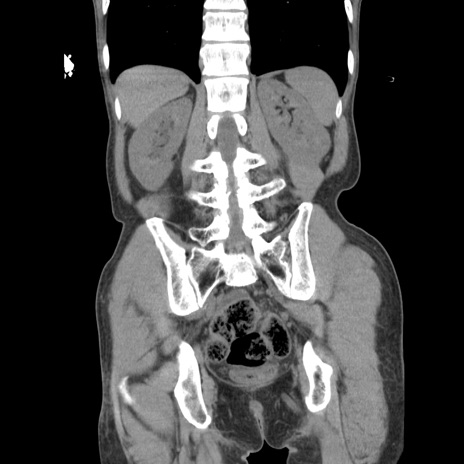

症例11(冠状断像)

【症例】 60歳代男性

【主訴】 下腹部痛

【現病歴】 本日夜中より下腹部痛の症状認め、受診。

【既往歴】 膀胱癌(膀胱全摘+尿管皮膚瘻術) 、胃癌術後

【身体所見】 BT 35.3℃、PR 58/min、BP 136/98mHg、腹部平坦、軟、腸蠕動音±、ストマ留置あり、左上腹部~正中部に圧痛あり、反跳痛なし。

【データ】WBC 5100、CRP0.01

横断像